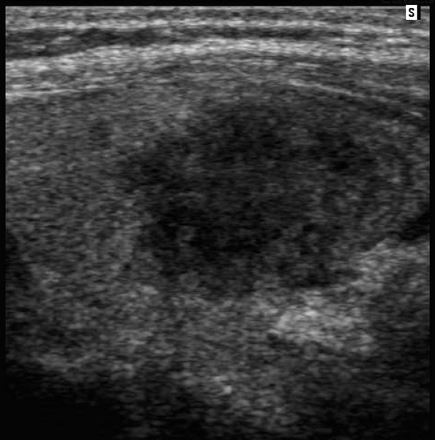

Tubular Ectasia of the Rete Testes

• The rete testes are a complex collection of small tubules that are located in the mediastinum of the testis. Fluid from the seminiferous tubules drains into the rete testis and then exits the rete testis via the efferent ductules. The efferent ductules then converge into the head of the

epididymis.

• Tubular ectasia of the rete testes is believed to be caused by some degree of outflow obstruction of the seminiferous fluid. Perhaps this is the reason why it is frequently associated with testicular cysts and spermatoceles of the epididymal head. It is also more commonly seen in patients with a history of inguinal surgery, such as hernia repairs and vasectomies.

• The key to making the diagnosis and distinguishing tubular ectasia of the rete testes from cystic testicular tumors is to note the bilateral involvement when present and to recognize the elongated shape on long-axis views of the testis.